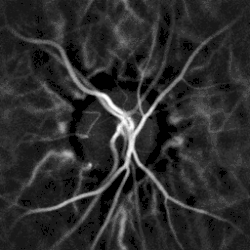

Laser Doppler holography

Computational imaging with lasers, ultrahigh-speed cameras, commodity graphics cards, and state-of-the-art statistical filtering algorithms, emerges as a competitive alternative to dye angiographies. This class of non-invasive microangiography techniques can be advantageously applied to the eye fundus to reveal endoluminal blood flow profiles in the retina and choroid.[6] Laser Doppler imaging by holography provides high-contrast visualization of local blood flow in choroidal vessels in humans, with a spatial resolution comparable to state-of-the-art indocyanine green angiography.